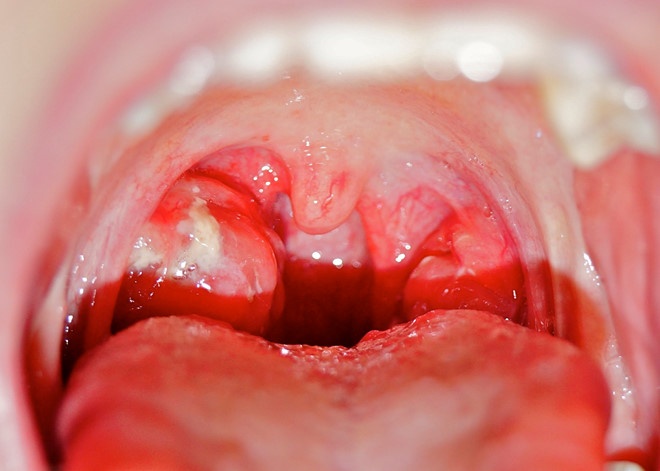

| Viêm họng cấp có thể gây ra một số biến chứng như viêm cầu thận cấp, thấp tim, viêm khớp cấp. Ảnh: Seoarticlelibrary . |